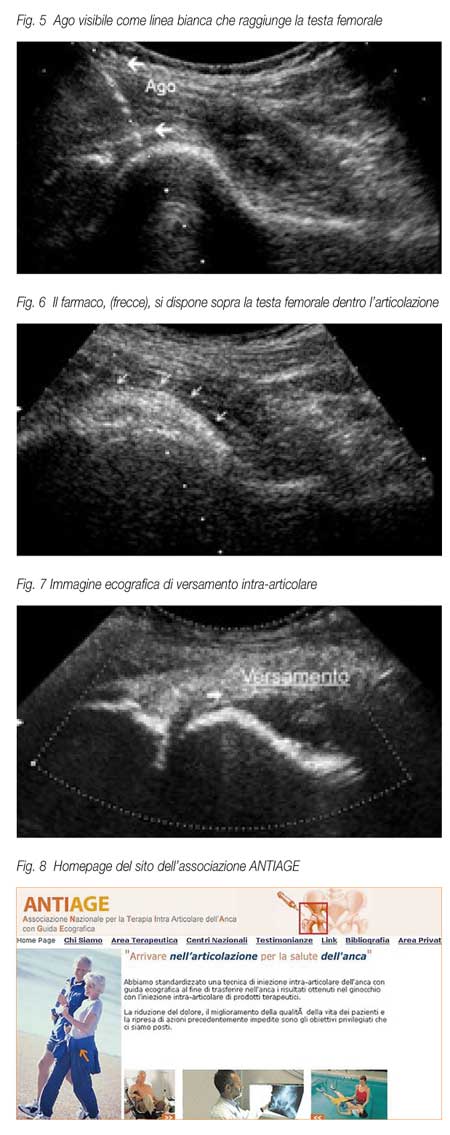

L’iniezione intra-articolare

si effettua inserendo nella guida bioptica un ago spinale

sottile (9-11cm) per via antero-superiore (fig. 4). Sul

monitor dell’ecografo è seguito in tempo reale

tutto il tragitto dell’ago ed il suo posizionamento

all’interno della articolazione sopra la testa del

femore (fig. 5); in questo punto l’acido ialuronico

o le altre sostanze medicamentose sono iniettate ed appaiono

visibili sullo schermo (fig. 6). La durata della metodica

e\o per il paziente. Va segnalato inoltre che in una percentuale

di casi non trascurabili (ca. il 10 % dei casi ) con l’ecografia

si è potuto evidenziare la presenza di versamento

articolare (Fig. 7),

di borsiti dell’ileopsoas.

di ipertrofia sinoviale, di corpi liberi intraarticolari.

Per estendere a tutto il territorio nazionale l’utilizzo

di questa tecnica iniettiva e la relativa terapia abbiamo

costituito l’ “Associazione Nazionale per la

Terapia Intra-articolare dell’Anca con Guida Ecografica

(ANTIAGE)” - ONLUS. L’associazione è

Ulteriori informazioni sono reperibili sul sito www.antiagefbf.it

(Fig.8).